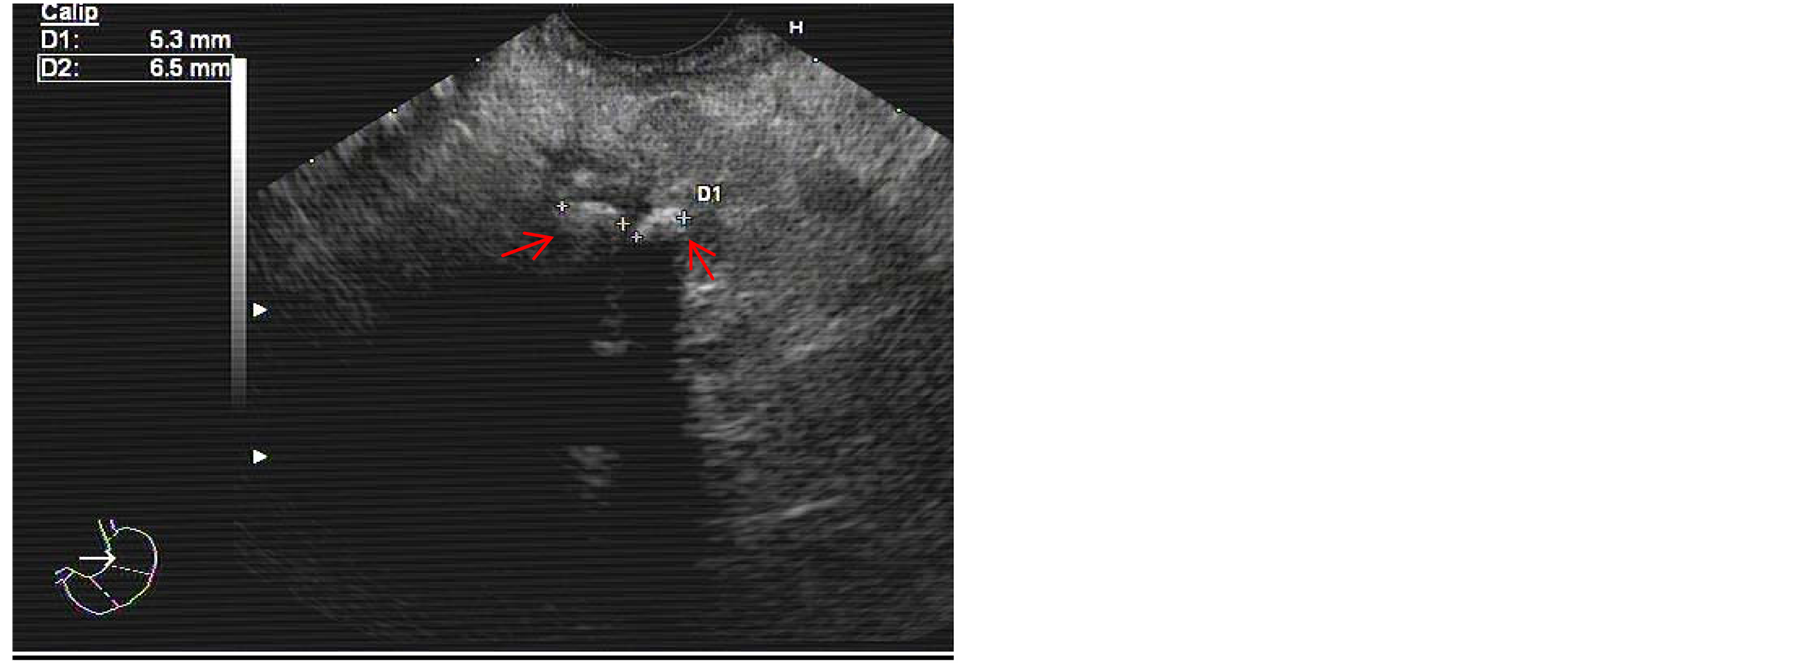

We present a case of a 52-year-old man with a past medical history of chronic pancreatitis requiring surgical necrosectomy who was admitted to our hospital due to a new exacerbation. Endoscopic ultrasonography demonstrated presence of lithiasis in the main pancreatic duct (Figure 1). Subsequently, ERCP with biliar sphincterotomy over a 0.035-inch diameter guidewire was performed, without difficulty. However, duodenal intubation was laborious due to repeated loop formation. Eventually, pancreatic tree canalization and pancreatic sphincterotomy were successfully realized. In spite of various attempts, it was impossible to extract the pancreatic stones.

Figure 1. Presence of two lithiasis in the main pancreatic duct (arrows) visualized by endoscopic ultrasonography.